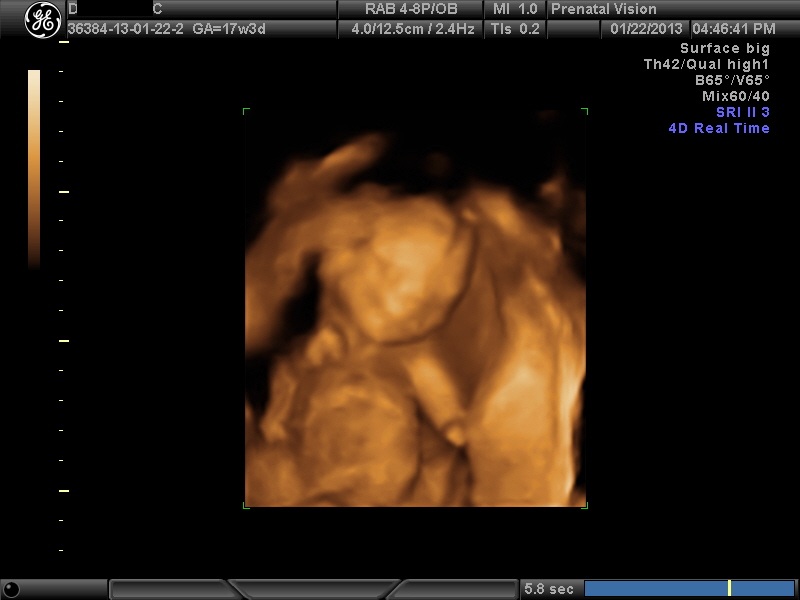

IMAGES_23 January 22, 2013 by Courtney Leave a comment ← Previous Image Next Image → 17w3d – Cooperating for the tech! Like Loading...